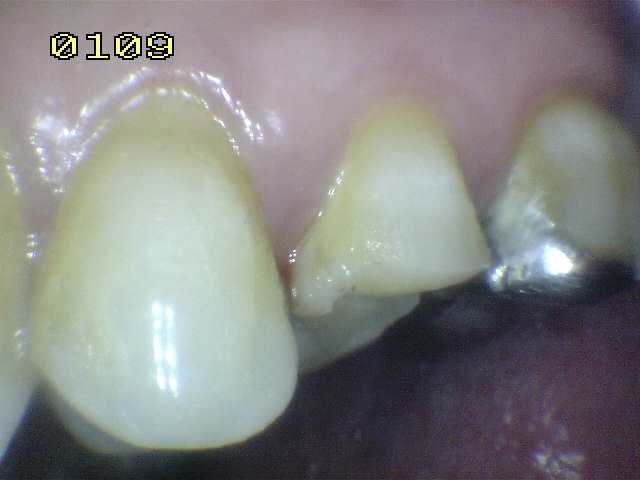

Pieza dental 25 para realizar tratamiento de conducto por necrosis Hecho el tratamiento de conducto, se elimina la totalidad de la amalgama Se bajan en altura las cúspide palatina, para evitar una futura fractura en tallo verde.

También se baja la cúspide vestibular o de corte , para prevenir una fractura dental.. Se coloca una matriz circular, se acuña y se bruñen los puntos de contacto y por ultimo se graba con acido durante 30 segundos. Se seca por 30 segundos, se aplica el agente de enlace y se activa con luz halógena por 20 segundos. La resina compuesta flow  es aplicada en la caja mesial y distal para fijar la matriz, una vez polimerizada.